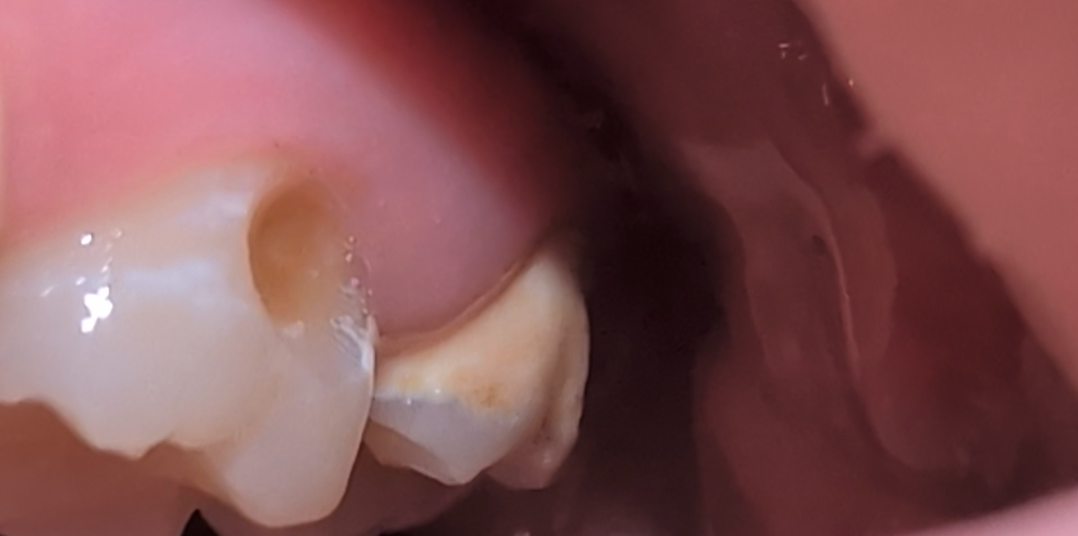

This all started with needing a few fillings and has snowballed into something much much worse. I've already been to the ER with pulpitis once and I couldn't afford it, and I may have to go again. I'm suffering daily headaches and sensitivity and it's hard to enjoy eating or drinking, let alone get out of bed.

I just need some help. I'm trying to get insurance to cover the root canals but they won't budge, and since I can't afford any better insurance and can't get enrolled in my job's insurance until October, it's even harder.